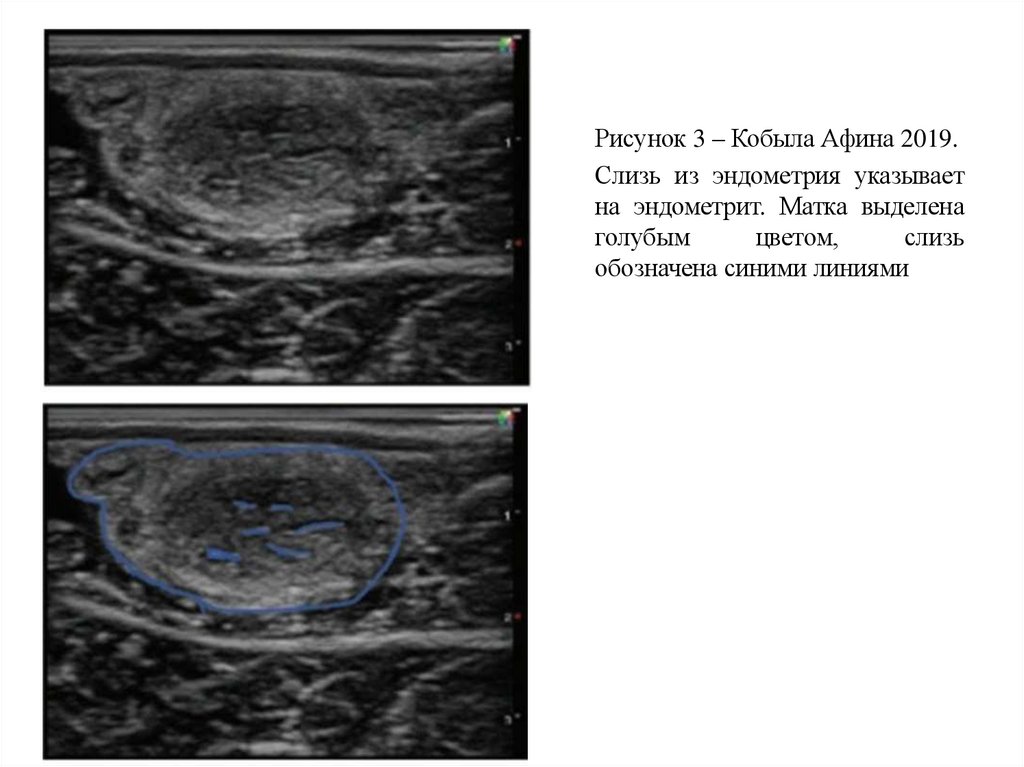

Рисунок 3 – Кобыла Афина 2019.

Слизь из эндометрия указывает

на эндометрит. Матка выделена

голубым

цветом,

слизь

обозначена синими линиями